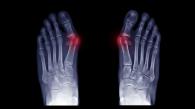

Appareillages d'Orteils : Orthoplasties

Les orthoplasties

Sont des appareillages d'orteils amovibles, sur mesure, destinés à traiter les déformations d'orteils et leurs conséquences.

Les orthoplasties correctrices corrigent une déformation réductible ou une malposition (sur ces photos)

Les orthoplasties protectrices protègent une zone douloureuse afin d’éviter les conflits peau/chaussure.